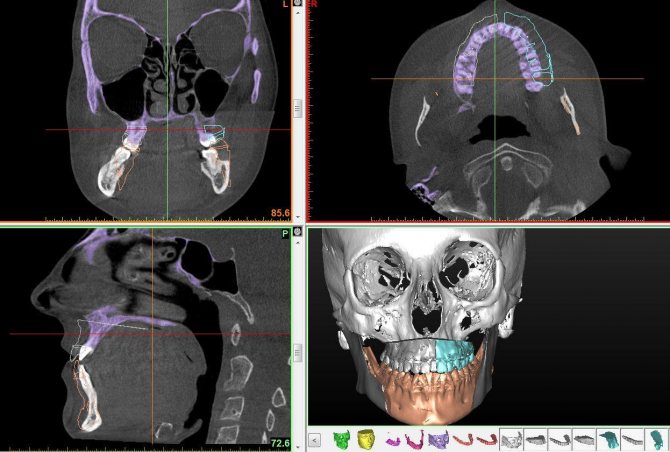

При подозрении на микрогинию пациенту делают ортопантомограмму, панорамный снимок зубочелюстного аппарата, на которую лечащий врач опирается при дальнейшем лечении.

- рентгенологическое исследование челюсти – снимки делают в нескольких проекциях;

- КТ, МРТ.

Первостепенным является проведение визуального осмотра, при котором врач выявит характерные внешние признаки. В дальнейшем пациента направят на проведение панорамного снимка (разновидность цифровой рентгенографии) и прохождение томографии.

Это даст полную информацию о состоянии подбородка и поможет выбрать наиболее подходящий метод устранения патологии.

Выяснить, что же вызвало нарушение прикуса, микрогнатия или макрогнатия, может прогнатия или норморетрогнатия, позволят современные методики. Одним и самых информативных методов считается телерентгенография. Она делается в боковой проекции. Тщательный анализ опытным специалистом сразу даст понять, в чем проблема: зубы или челюсти. Проблема в размере, пропорциональности или смещении?

Рассчитав рентгенцефалометрические показатели, можно их проанализировать, определить прикус, изготовить диагностическую модель челюсти пациента. Зачастую приходится прибегать к исследованию челюстных суставов и мышечной ткани. В этом случае наиболее информативным вариантом будет компьютерная томография.